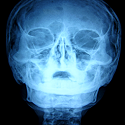

Un volumineux ostéome orbitaire : à propos d’un cas

Kamal Loutfi Nuiakh, Hicham Tahri

PAMJ. 2014; 18: 10. Published 02 May 2014